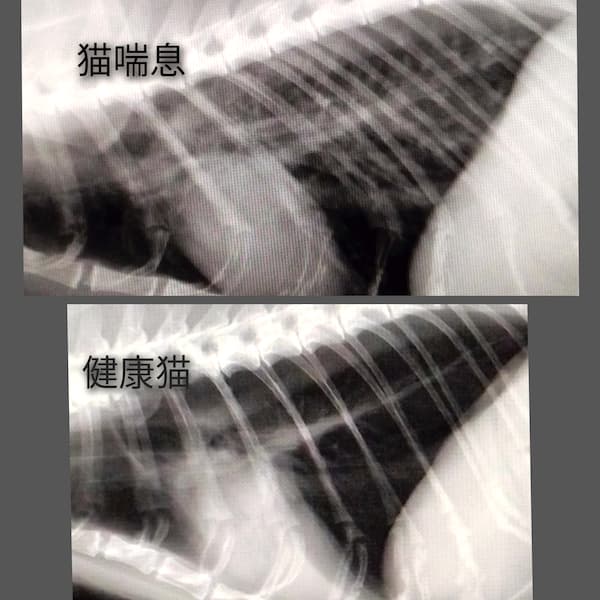

猫喘息(2025/07/14)

猫喘息は、何かしらの原因で気管支に慢性的な炎症があり、発咳、喘鳴(ゼーゼーという呼吸)、チアノーゼ等の呼吸障害を生じる疾患で、即時型アレルギーが関与しているとされています。胸部レントゲン検査、身体検査、血液検査などから総合的に診断します。治療には内服薬や注射薬の他、噴霧吸入療法(ネブライザー)や、飼育環境の整備などを行います。重症例では生涯に渡る治療が必要になることもあり、呼吸状態によっては命に関わる場合もあります。早期の治療介入により、重症化させないことが重要です。

猫の喘息(2024/02/23)

猫の喘息は、咳やえずき、ゼイゼイ・ヒューヒューと苦しそうな呼吸をする発作的な呼吸困難のことで、人の喘息に似ている病態です。発作が終わるとケロッとしていることが一般的ですが、進行すると命に関わる重大な病気です。血液検査やレントゲン検査などを行い総合的に診断します。 原因や発症の仕組みは明確には分かっていませんが、アレルギーによるものと考えられています。アレルギーの原因となるのは、ダニ、カビなどのハウスダスト、細菌、花粉、消臭剤、ヘアスプレー、たばこの煙、香水など、呼吸で吸い込むアレルゲンです。 猫喘息は完治することは難しく、喘息発作が出ないように、そして重篤化し命に関わる状態にならないよう生涯治療していく必要があります。咳や呼吸の異常など気になる症状がある場合はお早めにご相談ください。